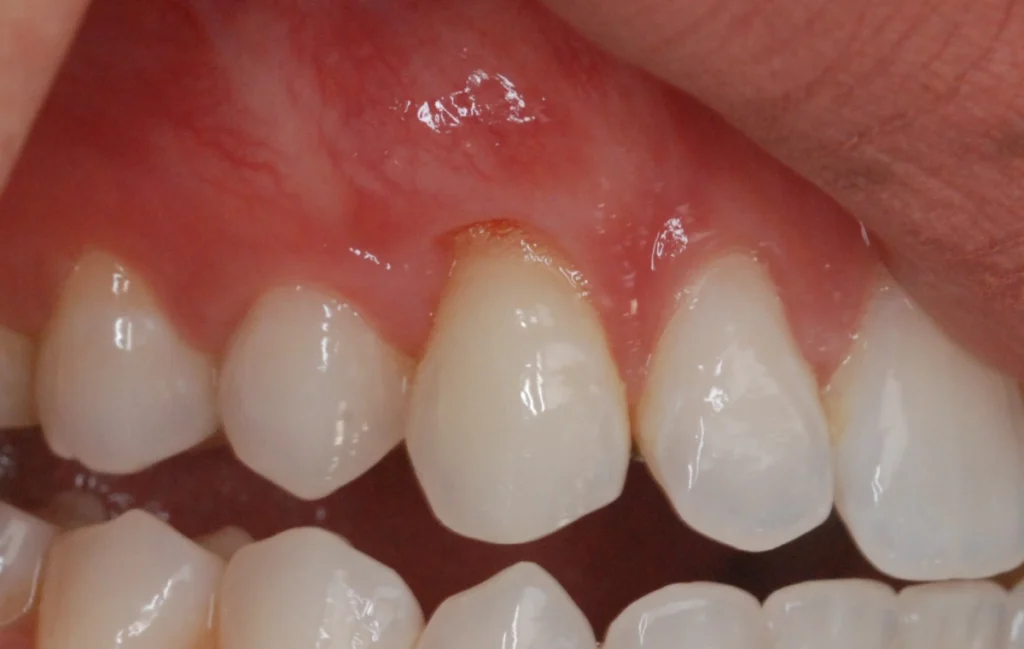

La récession gingivale

La récession gingivale est l’une des principales indications. Elle survient lorsque les gencives se rétractent, exposant les racines des dents. Cela peut être dû à un brossage agressif, à une maladie parodontale ou à un traumatisme. La chirurgie muco-gingivale couvre les racines exposées et renforce les gencives.

Cette chirurgie devient nécessaire lorsque les patients présentent des anomalies des gencives qui peuvent affecter la santé bucco-dentaire. Par exemple, la récession gingivale expose les racines des dents, augmentant le risque de caries et de sensibilité dentaire. En corrigeant ces défauts, la chirurgie muco-gingivale améliore non seulement la santé des gencives mais aussi l’esthétique du sourire.